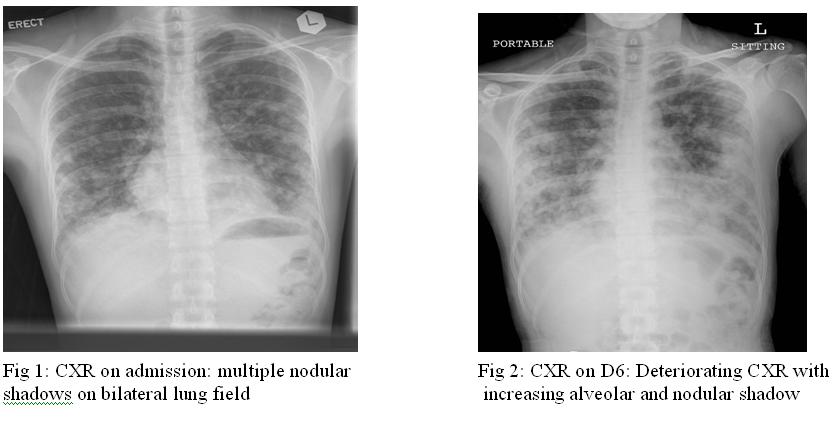

On examination, there was bilateral basal crepitations on auscultation. There was no cardiac murmur or lower limb oedema. JVP was not elevated. CXR on admission showed multiple nodular shadows on bilateral lung fields (Fig.1).

Concerning the imaging modalities, chest radiograph is useful in identifying the metastatic lung lesions. The features include multiple nodules, linear infiltrations, pleural effusion, diffuse alveolar shadow or pneumothorax.5 Contrast CT scan of thorax can identify the intracardial filling defect which has low attenuation. The metastatic lung lesions can be either nodular or cystic.6 Two dimensional echocardiogram and MRI scan offer no more specific findings. Confirmatory diagnosis still relies on tissue biopsy.